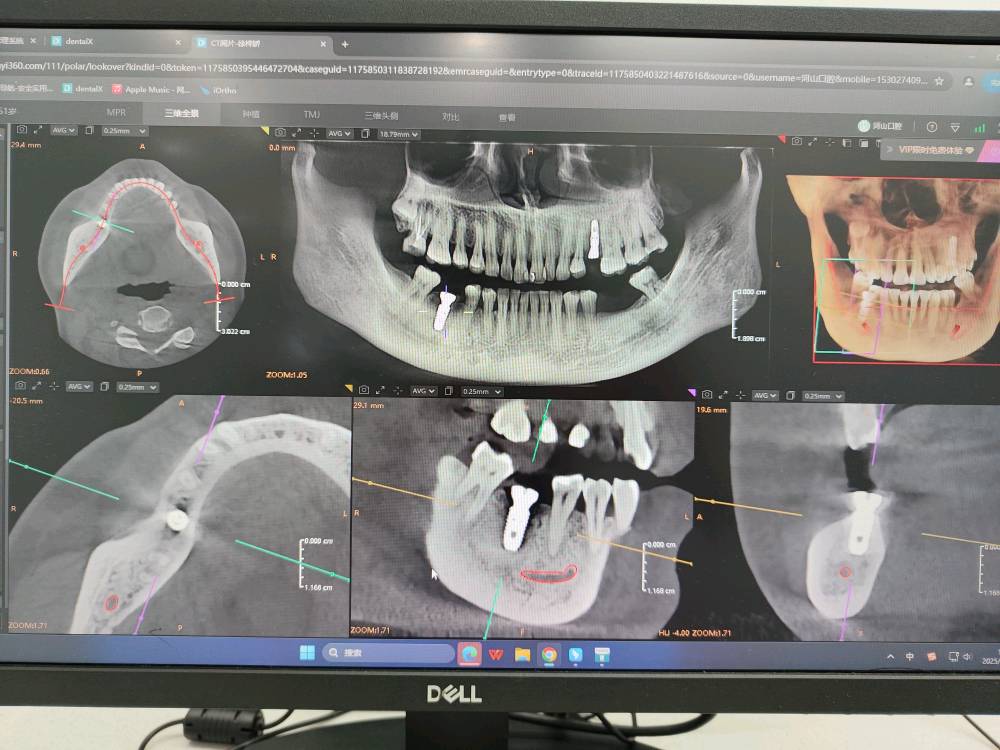

- 影像学检查:拍摄口腔全景片或CBCT(三维影像),评估骨量、神经位置。

- 制定方案:根据检查结果,选择种植体品牌,并制定个性化种植计划,安排手术时间。